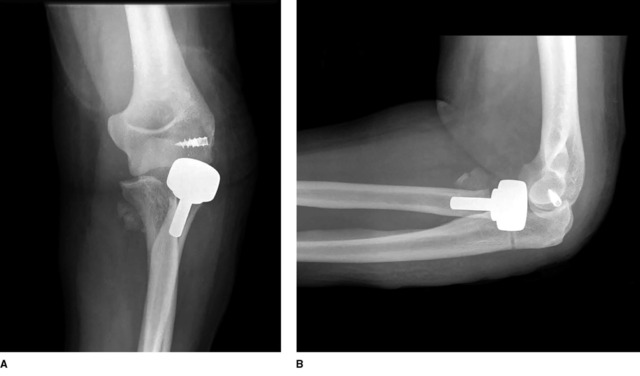

双极假体

双极桡骨头关节假体在桡骨头和桡骨颈的结合部位具有一个铰链结构(见图 7)。在肘关节的整个运动过程中,双极假体的桡骨头部件被认为可以更好的与肱骨小头匹配。最早由 Judet 等人进行的临床研究结果理想,12例患者的肘关节稳定性均获得恢复并且没有发生并发症。随后一些学者进行的中长期临床研究也取得了良好疗效。Celli 等人在 2010 年发表了一篇文章,16 例患者的平均随访 41.7 个月也证实了上述结论,87.5% 的新鲜桡骨头骨折患者通过双极桡骨头关节置换取得了满意的临床、功能和影像学结果。但是,该项研究同时报道了一种双极假体所独有的桡骨头关节置换并发症 -- 假体脱位。

截止目前,评估应用双极桡骨头假体置换的最大宗研究报道来自于 Zunkiewicz。他们治疗了 23 例新鲜桡骨头骨折和 7 例陈旧性肘关节损伤,平均随访 34 个月(范围 24 至 48 个月)。患者的平均 DASH 评分为 13.8,肘关节屈伸活动度平均为 126°。有 2 例患者需要进行二次手术,1 例是因为桡骨颈截骨不足而继发的关节过度填塞,1 例为肘关节不稳而需加用外支架固定。随访影像学检查没有发现肱桡关节出现退行性改变。和单极假体相比,双极桡骨头假体置换的治疗效果似乎更好,可以为桡骨头重建提供另外一种治疗选择,但是与之相关的假体脱位也是一个主要难题。需要注意的是,在尸体研究中,尤其是对于肘关节恐怖三联症,单极假体可以更好的对抗肱桡关节半脱位。

图 7 双极桡骨头关节假体。左侧为钛合金的假体柄,右侧为高分子的聚乙烯假体桡骨头